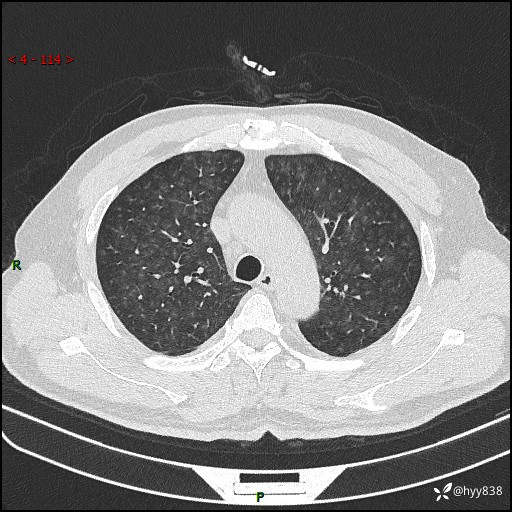

昨天肺结节门诊,“对门”呼吸科申请会诊病例,弥漫性肺部病变---结果公布~

主诉:发热、咳嗽、咳痰1周

简要病史:患者1周前无明显诱因出现咽喉部疼痛,随后出现咳嗽咳痰,起初干咳为主,后出现咳少许绿色痰,当时有发热,体温为39℃,无畏寒寒战,无胸闷胸痛,无活动后气短,无咯血,无鼻塞流涕,无全身酸痛,患者于诊所输液治疗后体温正常,但仍有咳嗽。患者3天前当地县人民医院就诊,患者仍有咳嗽,咳嗽较为频繁,咳嗽后出现头痛,伴有少许咳痰,随后出现活动后气短,1天前患者再次出现发热,体温最高为40℃,伴有畏寒寒战,伴有乏力、纳差,伴有胸闷不适,无咯血,无全身皮疹,无血尿、尿频尿急尿痛,无腹泻,诊断为“重症肺炎 感染性休克 肾功能异常 痛风”;予以抗感染(亚胺培南),抗病毒(奥司他韦)等对症治疗。患者复查胸部CT提示双肺病灶较前有所增多,建议上级医院就诊,门诊以“肺部感染”收入我科。 起病以来,患者食欲欠佳,大小便正常,睡眠、精神欠佳,体力下降、体重无明显变化。

辅助检查:CT

临床诊断:肺部感染

胸部HRCT